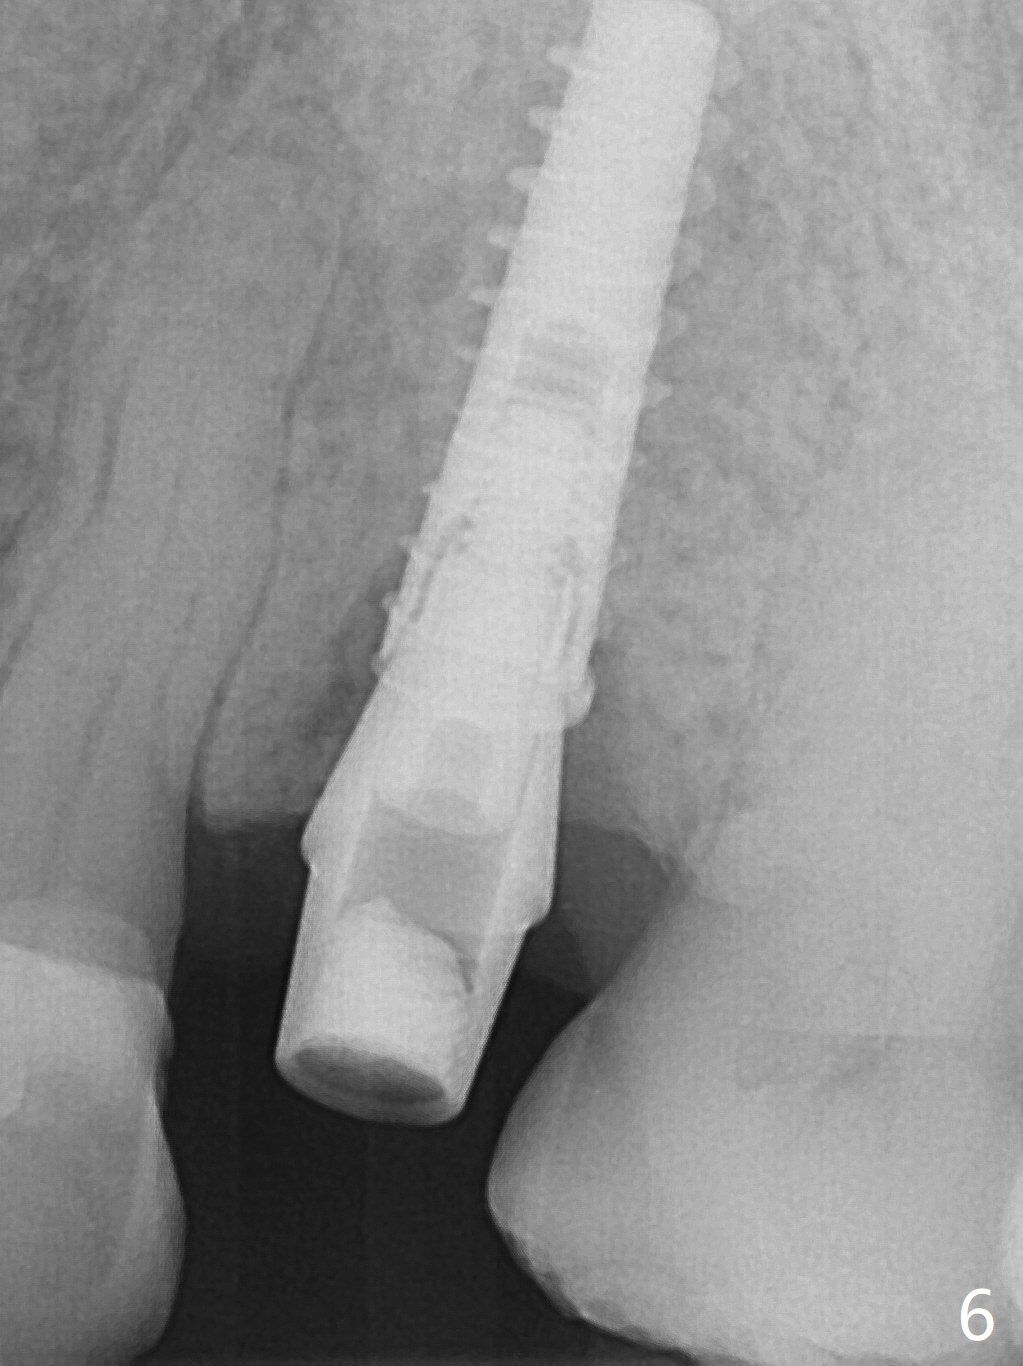

A 74-year-old man has diabetes. Implant osteointegration appears to be slow at #4, while the implant at #28 failed once. He requests implant at #13 (Fig.1). It seems that the bone is wide enough (8 mm, Fig.2 (CT coronal section) (P: palatal)) to hold a 4 mm implant (Fig.3 (axial section)). Since bone density is low at the coronal (100-200 units) and middle (50-100 units) segments (Fig.2), bone condensation will be beneficial. To facilitate wound healing, flapless approach is adopted using 1.6 mm pilot drill (Fig.4), followed by 1.4/2.6 mm bone expander. In fact there is resistance to expansion in the zone 1. Magic expander (3.0 mm) is also tried with difficulty. It appears that bone density is higher than expected. The second portion of Magic Surgical Kit is then used: 3.3 mm Magic Drill for 15 mm (gingival level, followed by Final Drill). A 4x13 mm IBS implant is seated incompletely. The osteotomy is further enlarged by 3.8 mm Magic Drill for 11 mm and deepened with 3 mm drill until 18 mm. Finally the implant is placed at a satisfactory level with insertion torque > 50 Ncm (Fig.5). A 4.5x4(3) mm abutment is placed and periodontal dressing is applied. The patient chooses to return for impression 6 months postop (Fig.6). The abutment changes to a 4x4(4) mm one. The crown is recemented nearly 2 years post cementation, which is related to distal and deep placement of the implant and bruxism (Fig.7).